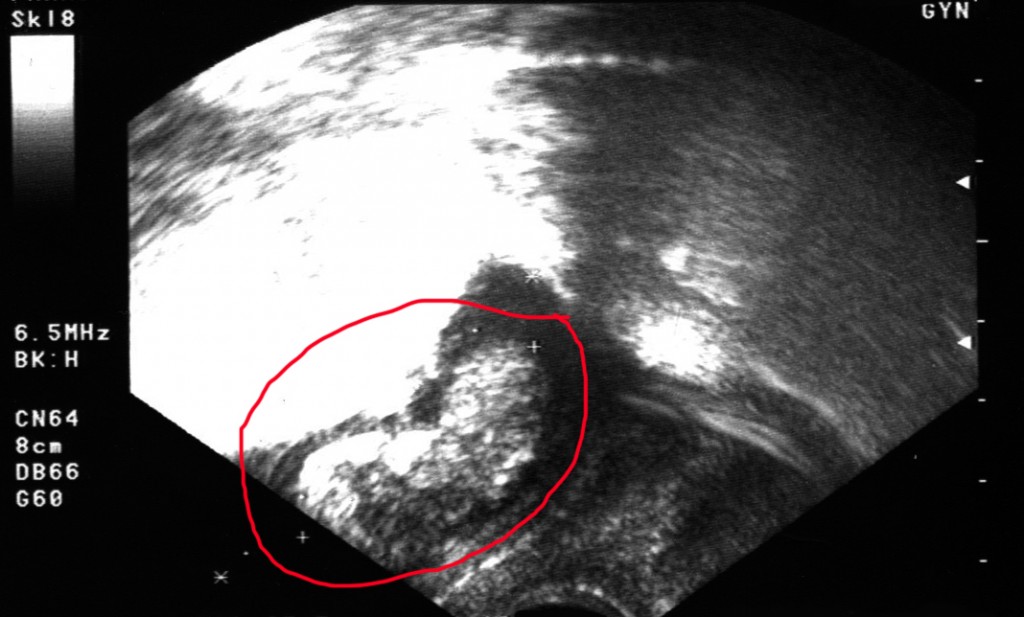

Ich bin jetzt am Ende der 11. Schwangerschaftswoche und habe heute endlich meinen Mutterpass bekommen. Der Termin bei meinem Gyn war unchristlich früh, wir (diesmal war mein Freund mit dabei) mussten schon um 6.30 Uhr aufstehen. Einplanen sollte ich eine gute Stunde, mir wurde jede Menge Blut abgezapft (Blutgruppenbestimmung, HIV-Test, Antikörper-Suchtest, Hb-Wert, und so weiter…), mein Blutdruck wurde gemessen, ich musste auf die Waage und in einen Becher pinkeln, außerdem durfte ich mich noch ausführlich von meinem Doc beraten lassen – es ging um Ernährung (Hauptsache ausgewogen, eh klar), Zahngesundheit (Karies kann eine Fehlgeburt auslösen – das wusste ich nicht) und natürlich darum, dass man als Schwangere auf Genussmittel tunlichst verzichten sollte – also kein Alkohol und keine Zigaretten (das wusste ich natürlich schon, aber er hat mir auch noch einmal genau erklärt, dass man eben nicht genau weiß, zu welchen Zeitpunkten in der Schwangerschaft Gifte den größten Schaden anrichten und dass man deshalb am Besten komplett darauf verzichtet). Am Ende durfte ich dann auf die Liege und es wurde der zweite Ultraschall gemacht – unglaublich, wie sehr sich das Würmchen schon weiter entwickelt hat: Man konnte jetzt schon deutlich die Extremitäten ausmachen und mein Freund hat sogar gesehen, wie es sich einmal um sich selbst gedreht und dabei mit den Ärmchen gerudert hat. Die Ausdrucke sind ja immer recht enttäuschend, weil die Bewegung fehlt, ich lade Euch meinen trotzdem hoch.